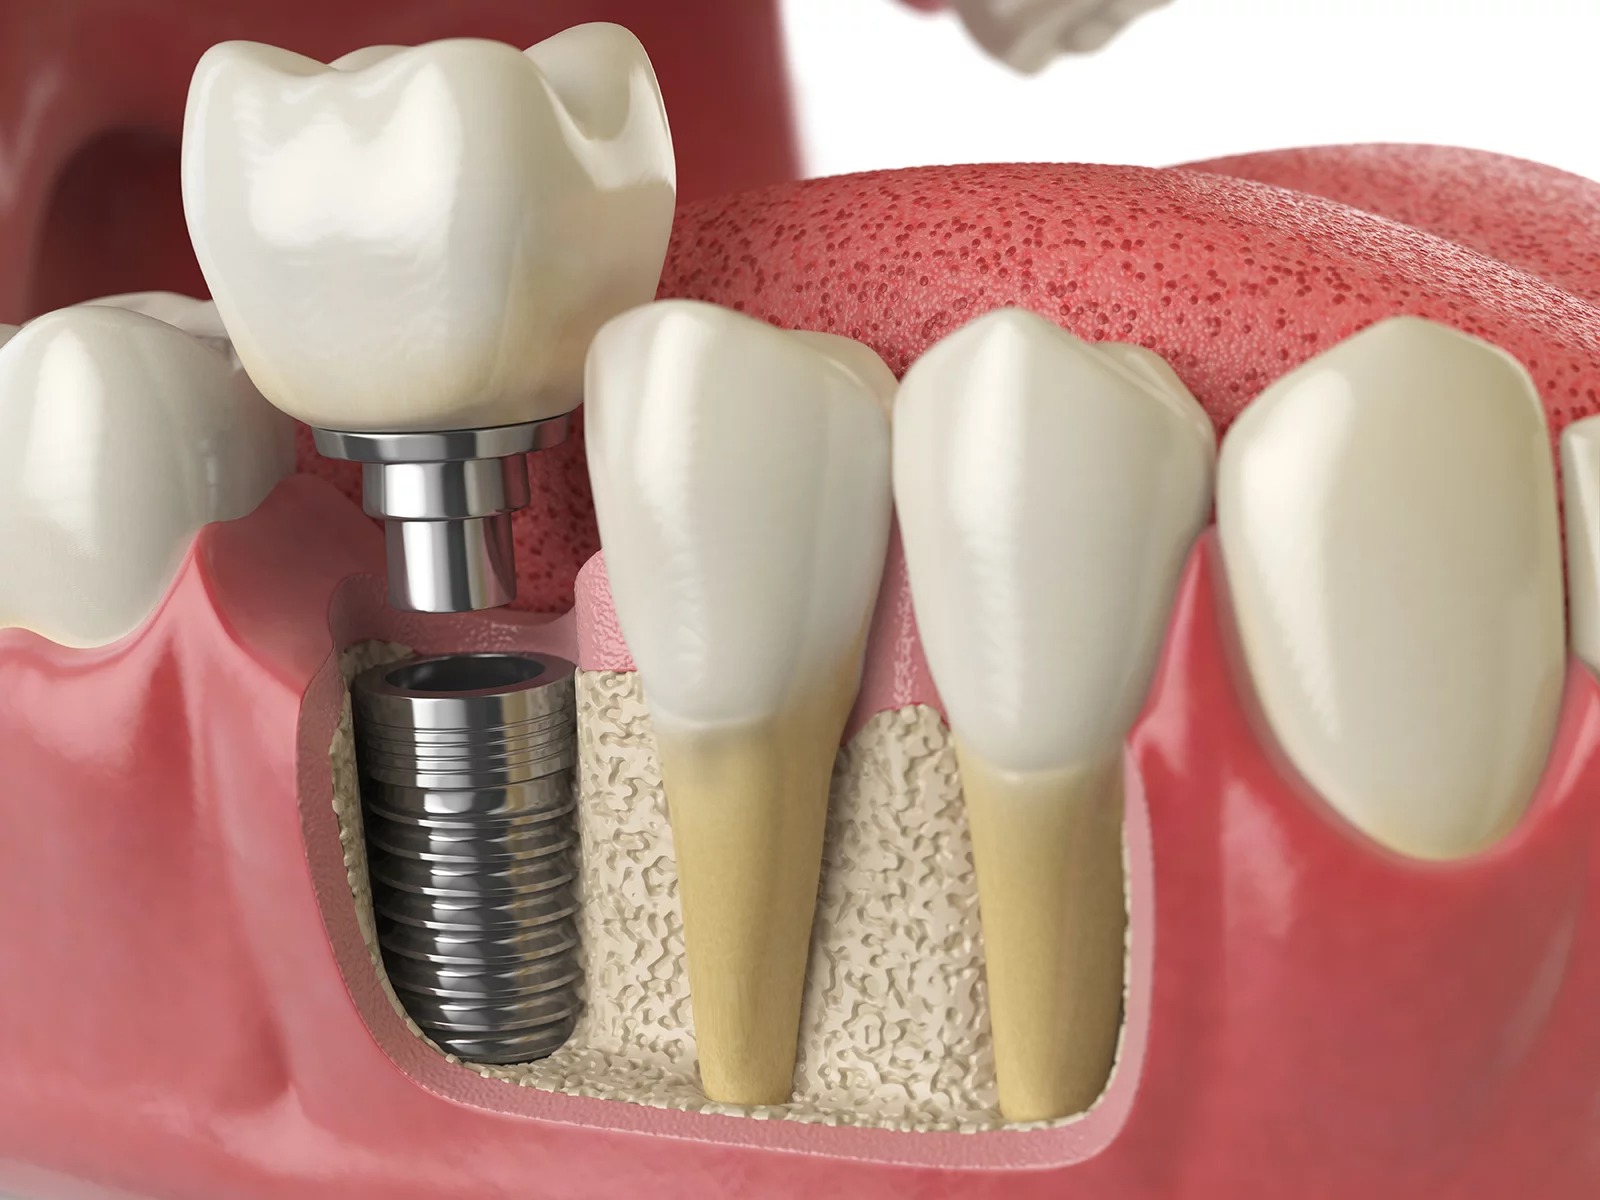

「オールオン4」とは

オールオン4は、片あごに最低4本のインプラントを埋め込んで、全ての歯(12本)を支える治療法です。1歩1本インプラントを埋めるよりも本数が少ない分だけ、費用を抑えることができます。また、基本的に手術は1回で済むので、身体的負担が軽減されます。

必要に応じて6本のインプラントを使用することもあります。

一般的なインプラント治療との違いは次のとおりです。